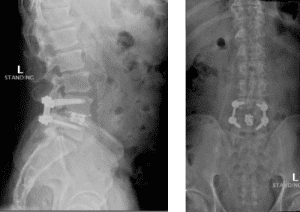

The grade 1 spondylolisthesis at L4/L5 requires both decompression at the L4/L5 level but also fusion because of the instability with motions. Here are three standing x-rays: one in the neutral position, one in flexion, and one in extensions. Notice the movement in the vertebral bodies at L4 and L5. This is abnormal motion and it can contribute to back pain and increase stenosis in certain positions. Thus, it requires decompression and stabilization with fusions.

Image 2. This shows the lumbar spine in motion. Notice the L4 and L5 level changes with flexion and extension. Notice the L2 and L3 levels do not have that type of motion. This is instability.

Image 3. Post-op x-rays that show L4/L5 transforaminal lumbar interbody fusion (TLIF). There was also removal the L2/L3 disc herniation but no need for instrumentation.